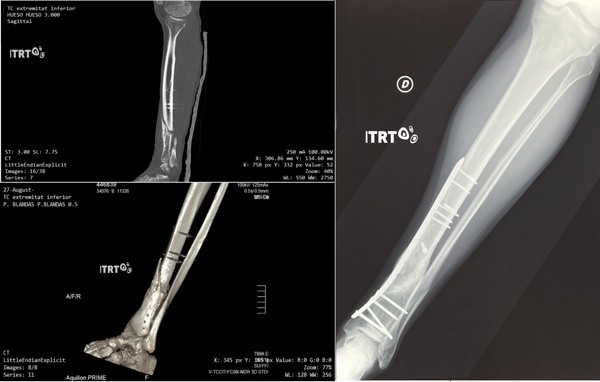

Aquesta patologia es produeix quan l'os no és capaç de consolidar o reparar una fractura. La lesió s’acostuma a detectar quan el pacient no recupera la mobilitat normal després d'una cirurgia, un cop transcorregut el temps estimat de curació, o bé perquè senzillament l'os torna a fracturar-se.

L'Institut de Teràpia Regenerativa Tissular (ITRT) ha demostrat en 3 assaigs clínics diferents que el tractament amb cèl·lules mare mesenquimals cultivades (CMMC), genera nou os i recupera la lesió. L'os es regenera en fractures que no consoliden amb resultats sense precedents que milloren àmpliament l'abordatge quirúrgic tradicional.

La Pseudoartrosi pot afectar diferents ossos de el cos, tot i que ITRT té experiència en el tractament en tots ells, especialment fèmur, tíbia i peroné, húmer o clavícula. Alguns dels esportistes d'elit més coneguts a nivell internacional en esports com motociclisme o bàsquet se n'han beneficiat.